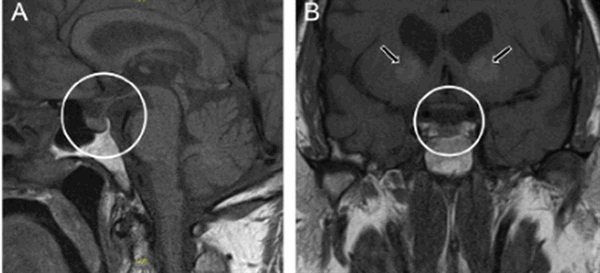

МРТ гипофиза. На МР-томограмме определяется гигантское образование неоднородной структуры (обведено) — макроаденома гипофиза.

МРТ гипофиза (обведено) без контраста и с с контрастом. В норме гипофиз равномерно накапливает контрастное вещество — становится светлым.

МРТ гипофиза с контрастом. После введения контрастного вещества в гипофизе происходит его накопления и он выглядит светлым. Только участок опухоли не накапливает контрастное вещество и выглятит темным (стрелка).

МРТ гипофиза с контрастом и без: А- гипофиз нормальных размеров (обведено кругом), В - симметричные кальцификации (стрелки)